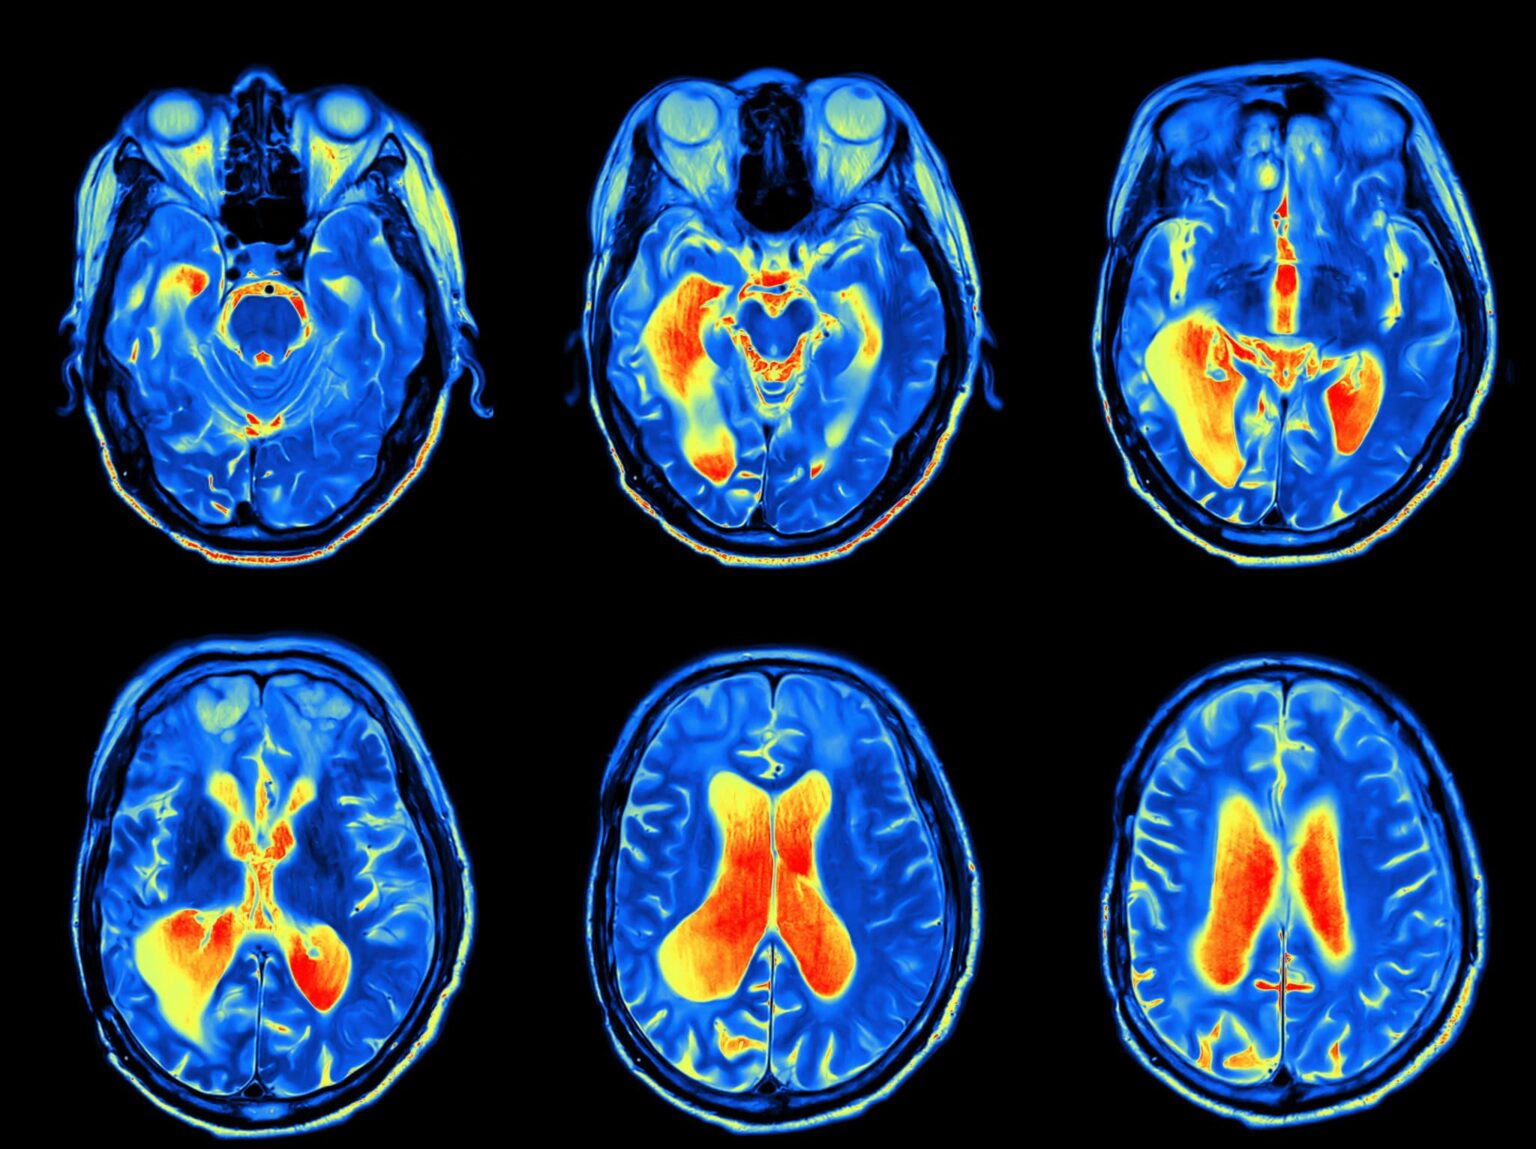

Our otolaryngologist will begin by discussing your symptoms and their impact on your daily life and performing physical and neurological examinations. They may also perform a CT scan, MRI, bone scan and positron emission tomography (PET) scan.